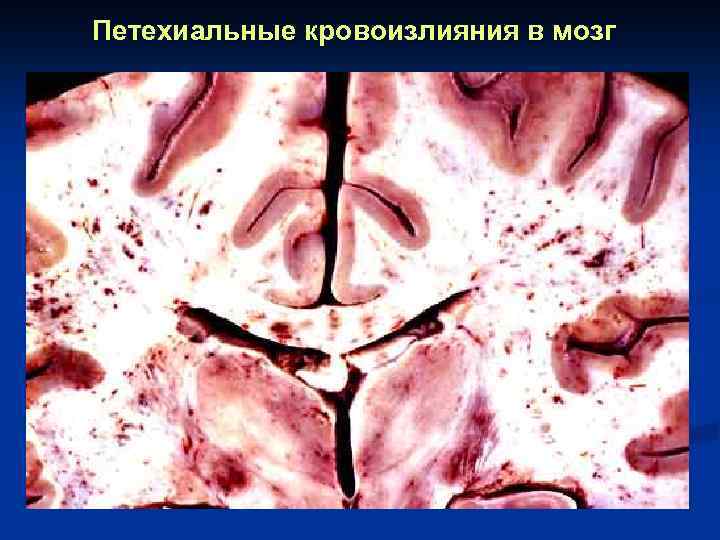

Петехиальные кровоизлияния в мозг

Петехиальные кровоизлияния в мозг